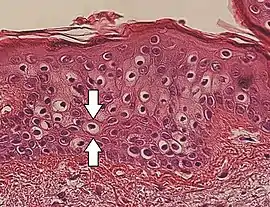

Perinuclear vacuolization of epidermal keratinocytes (one indicated by arrows), in this case an insignificant incidental finding.

Vacuolization is the formation of vacuoles or vacuole-like structures, within or adjacent to cells. Perinuclear vacuolization of epidermal keratinocytes is most likely inconsequential when not observed in combination with other pathologic findings. In dermatopathology "vacuolization" often refers specifically to vacuoles in the basal cell-basement membrane zone area, where it is an unspecific sign of disease.[1] It may be a sign of for example vacuolar interface dermatitis, which in turn has many causes.

It is one of the components of koilocytosis, which may be present in potentially pre-cancerous cervical, oral and anal lesions.[2]